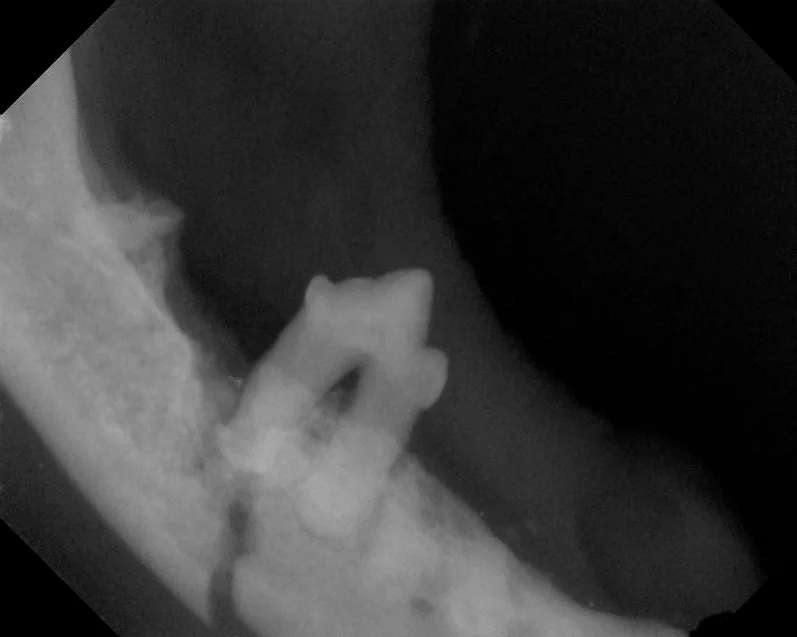

This tooth was fractured at the outside crown of the tooth (see arrow). Dental x-rays of the tooth showed significant infection (dark area circled) at the root of the tooth. Having this information helped plan the proper extraction technique of this badly damaged tooth.